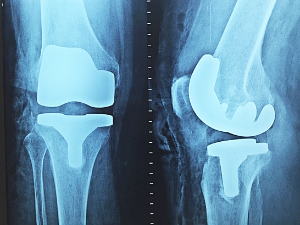

6. 퇴행성 관절염

퇴행성 관절염은 나이가 들어가면서 뼈, 인대, 근육 등의 조직이 퇴행하고 연골이 점차적으로 닳아서 염증이 발생하여 통증을 유발하는 상태를 말합니다. 주로 노년층에서 발생하는 이 질환은 노화와 밀접한 관련이 있습니다. 대부분 무릎에서 증상이 나타나지만, 어깨, 손가락, 척추 등 다른 관절 부위에서도 발생할 수 있어 항상 주의해야 합니다.